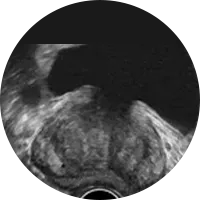

A obtenção de imagens por RM Aberta não envolve a utilização de Raios-X, ou mesmo material radioactivo e praticamente não necessita de preparação. As imagens adquiridas, resultam da interacção entre o campo magnético e os átomos que fazem parte das nossas células.

As imagens são formadas por um computador, que processa os sinais que são emitidos pelos tecidos do corpo humano. Este sinal é gerado, usando um campo magnético em combinação com pulsos de radiofrequência. As diferentes características dos tecidos são reveladas através deste processo e traduzidas em diferentes níveis de contraste na imagem.